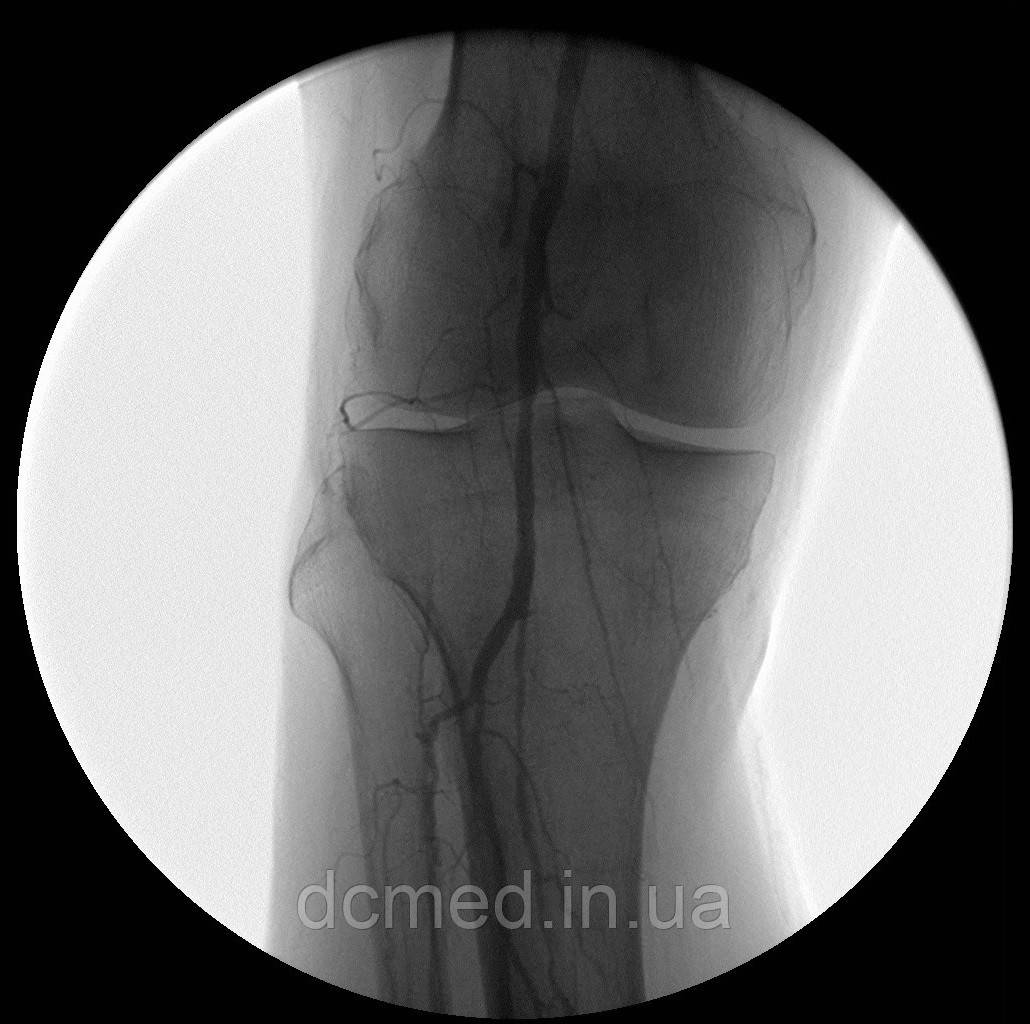

- цифрова субтракційна ангіографія (DSA) 25 кадр/с;